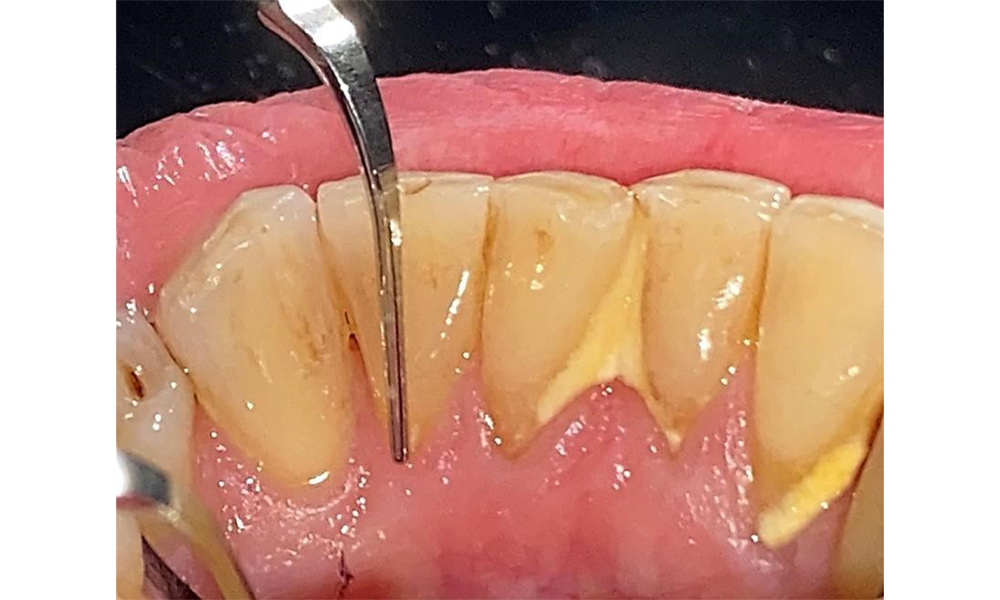

The patient has stage II, grade B periodontitis (5). At 1 to 3 mm, the clinical probing depths were within the physiological range. Localized probing depths of 5 mm were observed on the mesiopalatal aspects on both 17 and 27. There are generalized recessions of 1–3 mm with partial loss of the interdental papillae (Fig. 2, Fig. 3, Fig. 4)

There are no limitations regarding the choice of instrumentation methods. Regular supragingival and subgingival instrumentation is essential to prevent disease progression due to the pre-existing periodontitis and high risk of recurrence. There are no limitations placed on the selection of instruments for mechanical biofilm removal from a general medical perspective, and removal should be performed as needed. Hard and mineralized plaque, such as calculus and concretions, should be removed using manual instruments or sonic/ultrasonic scalers (Fig. 9) (8, 9).